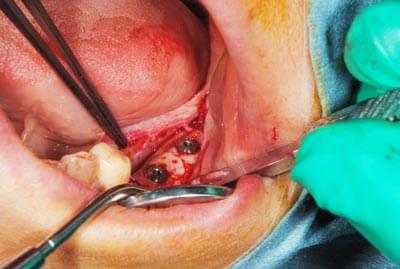

インプラントを埋入するためには、骨を増やさなければならず、患者様ご自身の骨を移植する、自家骨移植術を行なうこととしました。写真、青色の矢印で示す、智歯周辺の骨を採取し、黄色の矢印の部位に骨片を移植、チタン製の小さなスクリューで骨片を固定するという手術を行いました。細く、白く映っているのが骨を固定したミニスクリューです。

写真は、実際の手術の写真で、丸く採取された骨片が、スクリューで固定されています。